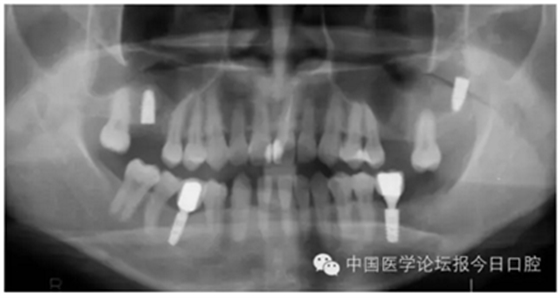

病例9 種植體進(jìn)入額竇腔內(nèi)(圖11)

圖11

?、芊N植體植入上頜竇或其他竇腔的情況較少見,但可能在患者為Ⅳ類骨或骨量少時(shí)發(fā)生,5~6mm骨量時(shí)也可能發(fā)生(如圖11所示)。